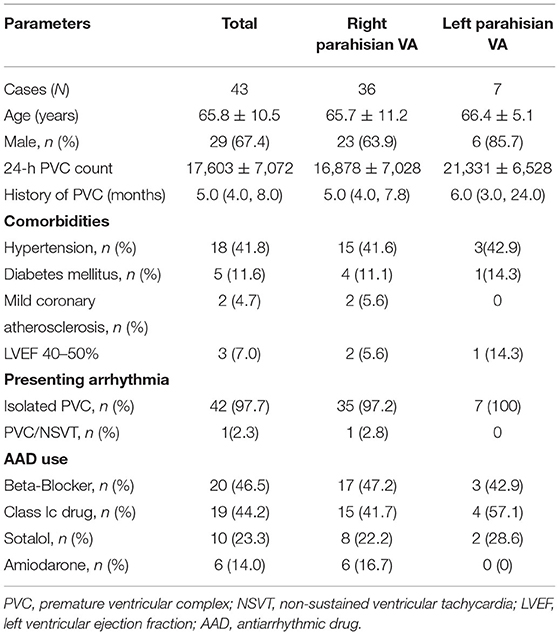

Forty-three patients (29 males; average age 65.8 ± 10.5 years) with PHVAs were enrolled to undergo catheter ablation from January 2017 to September 2020. PHVAs were diagnosed according to surface electrocardiograms (ECGs) (3–5), which typically manifested QRS discordance in inferior leads (lead II/III/aVF), “QS”/“Qr”/“qR”pattern in lead V1, and precordial transition earlier than lead V3/V4 (Figure 1A). Inclusion criteria were symptomatic monomorphic VAs; daily PVC burden > 10% or total PVC exceeding 10,000 per day or concomitant with VT of identical morphology; refractory or intolerance to at least one antiarrhythmic drug (AAD), including beta-blockers, Class Ic and Class III AADs. Exclusion criteria were ischemic heart disease; primary cardiomyopathy; prior cardiac surgery; congenital heart disease. All patients provided written informed consent for the ablation.

Figure 1. Examples of PHVA electrocardiograms and the flow chart of the systemic mapping approach. (A) Typical twelve-lead electrocardiographic manifestation of parahisian VAs. Right parahisian VAs were diagnosed in Case 1–5, and left parahisian VA in Case 6. Note there were positive “R” waves/or QRS discordance in inferior leads, a “QS” wave in lead V1, precordial transition in lead V2–V4 for right parahisian VAs, and a “qR” wave in lead V1 and precordial transition in lead V1–V2 for left parahisian VA. (B) The flow chart of the systemic mapping approach for right and left parahisian VA.

The Protocol of Systemic Mapping Approach for PHVAs

The protocol of systemic mapping approach was shown in Figure 1B. Briefly, it could be described as three steps. Step 1: Pre-judgement of left or right PHVAs according to the QRS morphology in lead V1 and precordial transitional zone (13). The “R”/“qR(s)” pattern in V1 and precordial transitional zone ≤ V1 indicated a left PHVA. The “QS”/“rS” pattern in V1 and precordial transitional zone ≥ V2 indicated a right PHVA. Step 2: Initial ablation based on the results of parahisian mapping. For right PHVA, the B-SLTV approach was performed in all patients. For left PHVA, ablation was performed above or below the aortic valve based on the mapping results. Step 3: Subsequent mapping and ablation if the initial ablation failed, including A-SLTV ablation and anatomical ablation at the contralateral parahisian region and the adjacent structures.